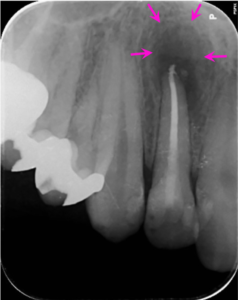

治療後1ヶ月

根の治療終了1か月後にグラスファイバーの芯棒を用いた歯の土台(根の治療を行った場合に行う治療です)を立て、その上にコンポジットレジンにて修復を行なった際のレントゲン写真です。根の先の骨の溶けている部分の大きさはさらに縮小傾向が見られます。歯の根の治療の後は通常は歯のかぶせによって治療を完了しますが、前歯で残存歯質が十分にあり、この患者様はたくさん歯質を削るかぶせの治療を希望されませんでしたので、このような治療を行いました。

治療後6ヶ月

根の治療6か月後のレントゲン写真です。矢印の骨の溶けている部分の大きさが小さく、境界も不明瞭になり、回復してきています。